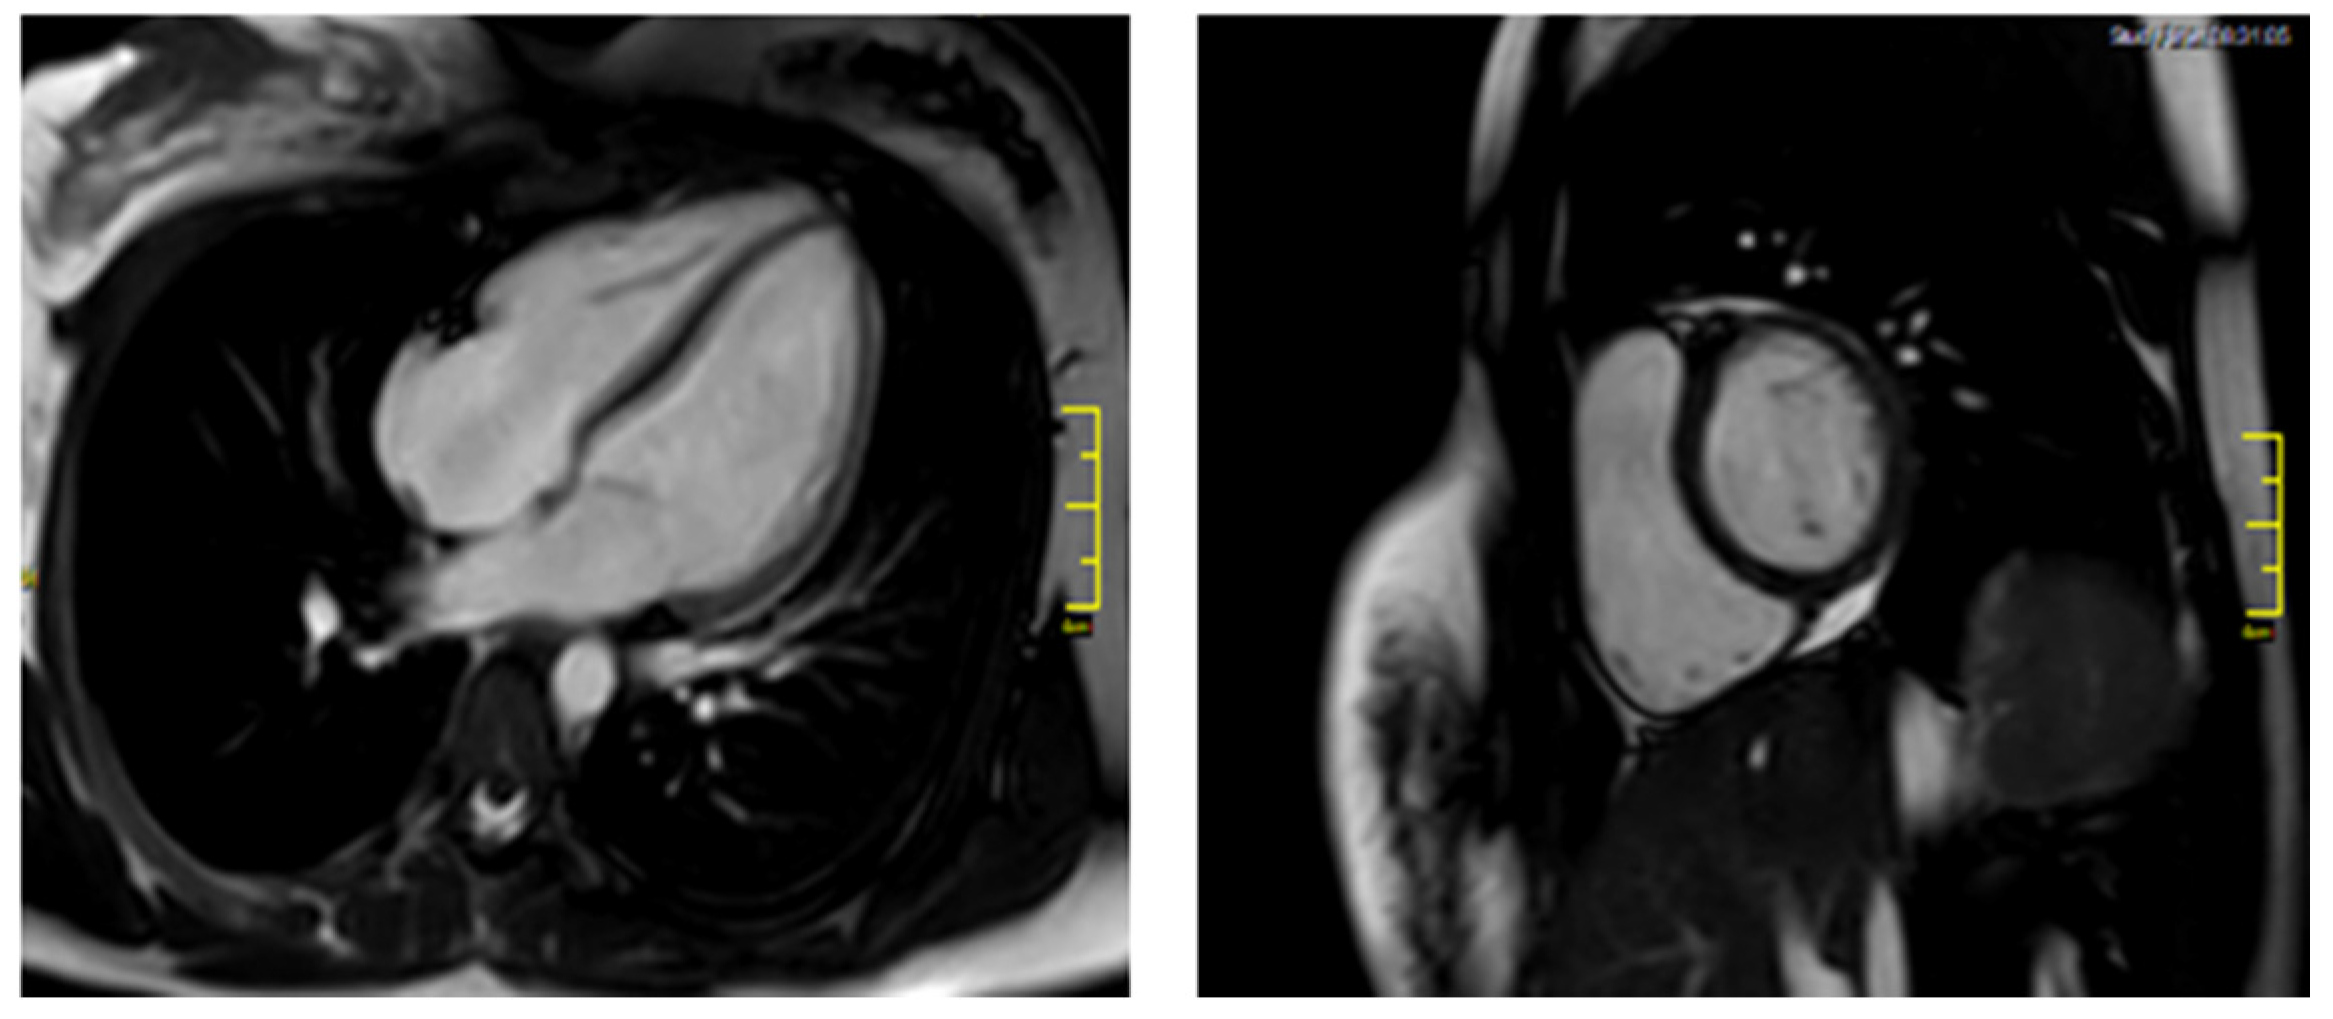

| Echocardiography | Normal | Normal | Normal | Normal | |||